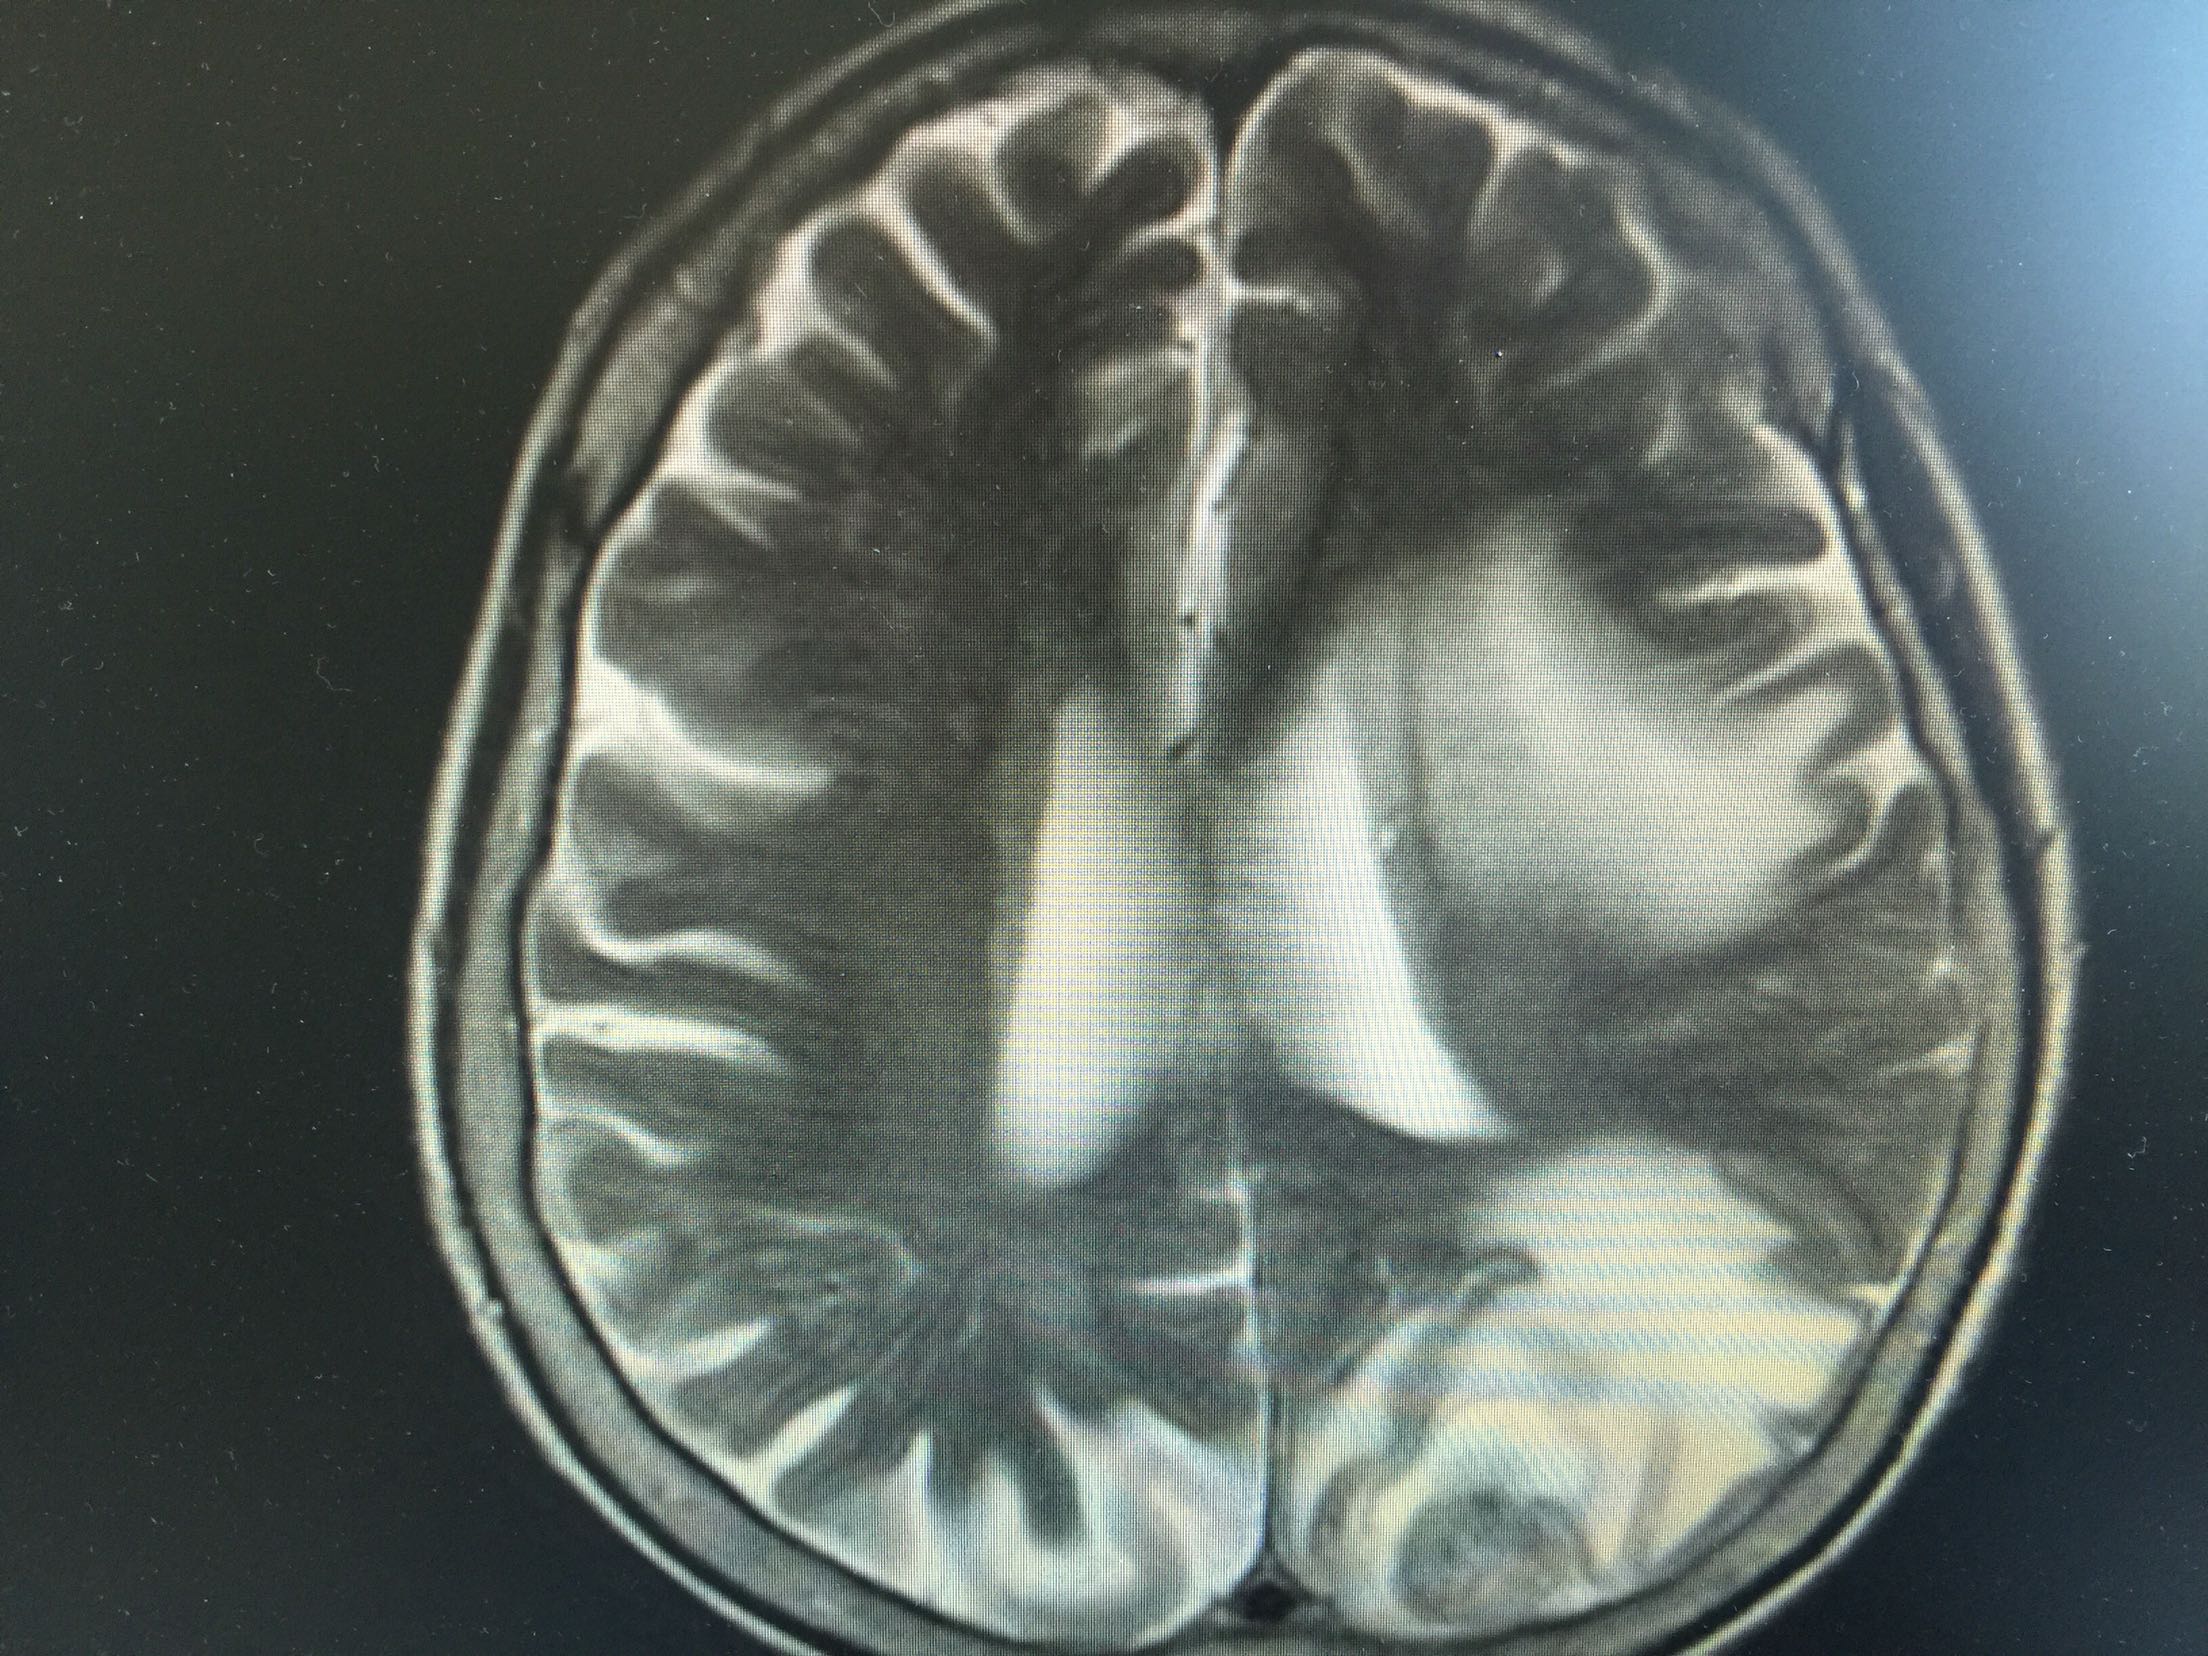

1.女,81岁,以“右侧肢体无力3天”入院。 2.现病史:3天前无诱因出现右侧肢体无力,右上肢抬举费力,右下肢步行拖拉,无抽搐,无意识障碍! 3.既往史:2016年肺穿刺活检,免疫组化为腺癌!已合并第五、六椎体转移、左肾上腺转移,行灌注介入治疗。

查体:血压:130/80mmHg,两肺呼吸音清,未闻及啰音,心率98次/分,律齐,未及杂音,双下肢无水肿。神经系统查体:意识清,双侧瞳孔等大正圆,直径约3.0mm,对光反射灵敏,无面舌瘫,右侧肢体肌力4级,腱反射减弱,Babinski征R+L-。

左肺腺癌 骨转移、双肺门及纵膈淋巴结转移、左肾上腺转移、脑转移! 治疗:对称、支持治疗!